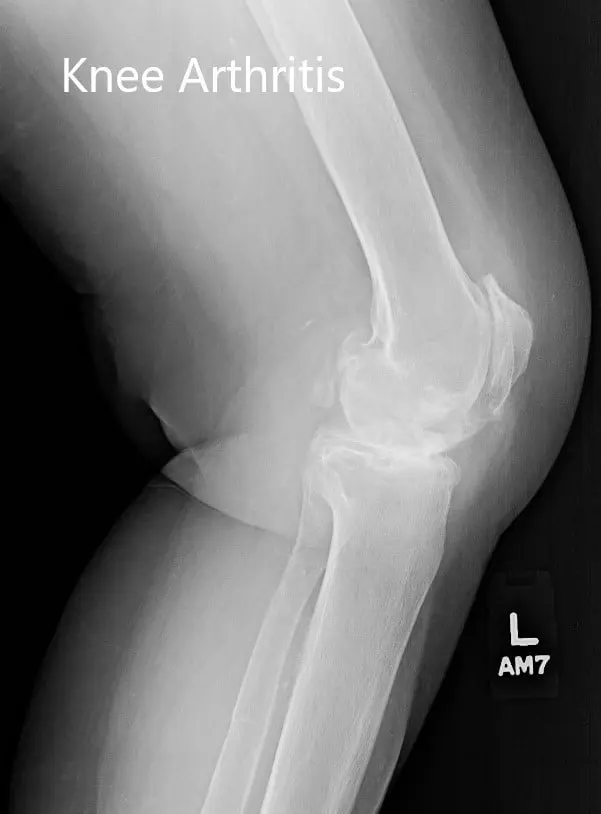

Imaging studies revealed severe bilateral osteoarthritis. The left knee was worse than the right knee. Considering the patient’s lifestyle limiting knee pain, he was advised left total knee replacement. Risks, benefits, and alternatives were discussed at length with the patient and his son. He decided to go ahead with the procedure.

Preoperative X-ray of the left knee showing severe osteoarthritis in anteroposterior and lateral views.